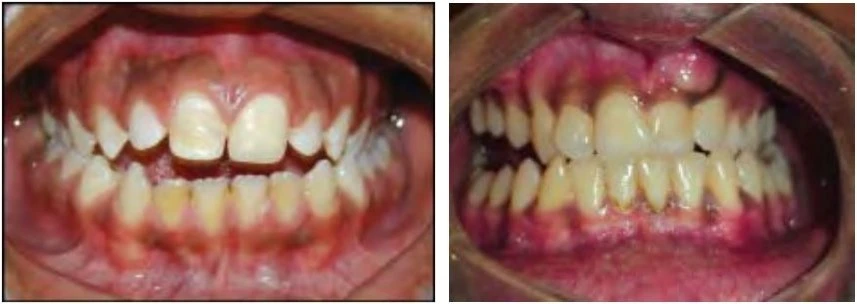

2.2 SAI KHỚP CẮN THEO MẶT PHẲNG ĐỨNG NGANG

Trường hợp này có thể chia làm hai phân loại tùy thuộc vào độ phủ theo chiều dọc của các răng giữa hai hàm.

Cắn sâu

Với loại này, độ cắn phủ theo chiều dọc giữa răng hàm trên và răng hàm dưới lớn hơn so với bình thường.